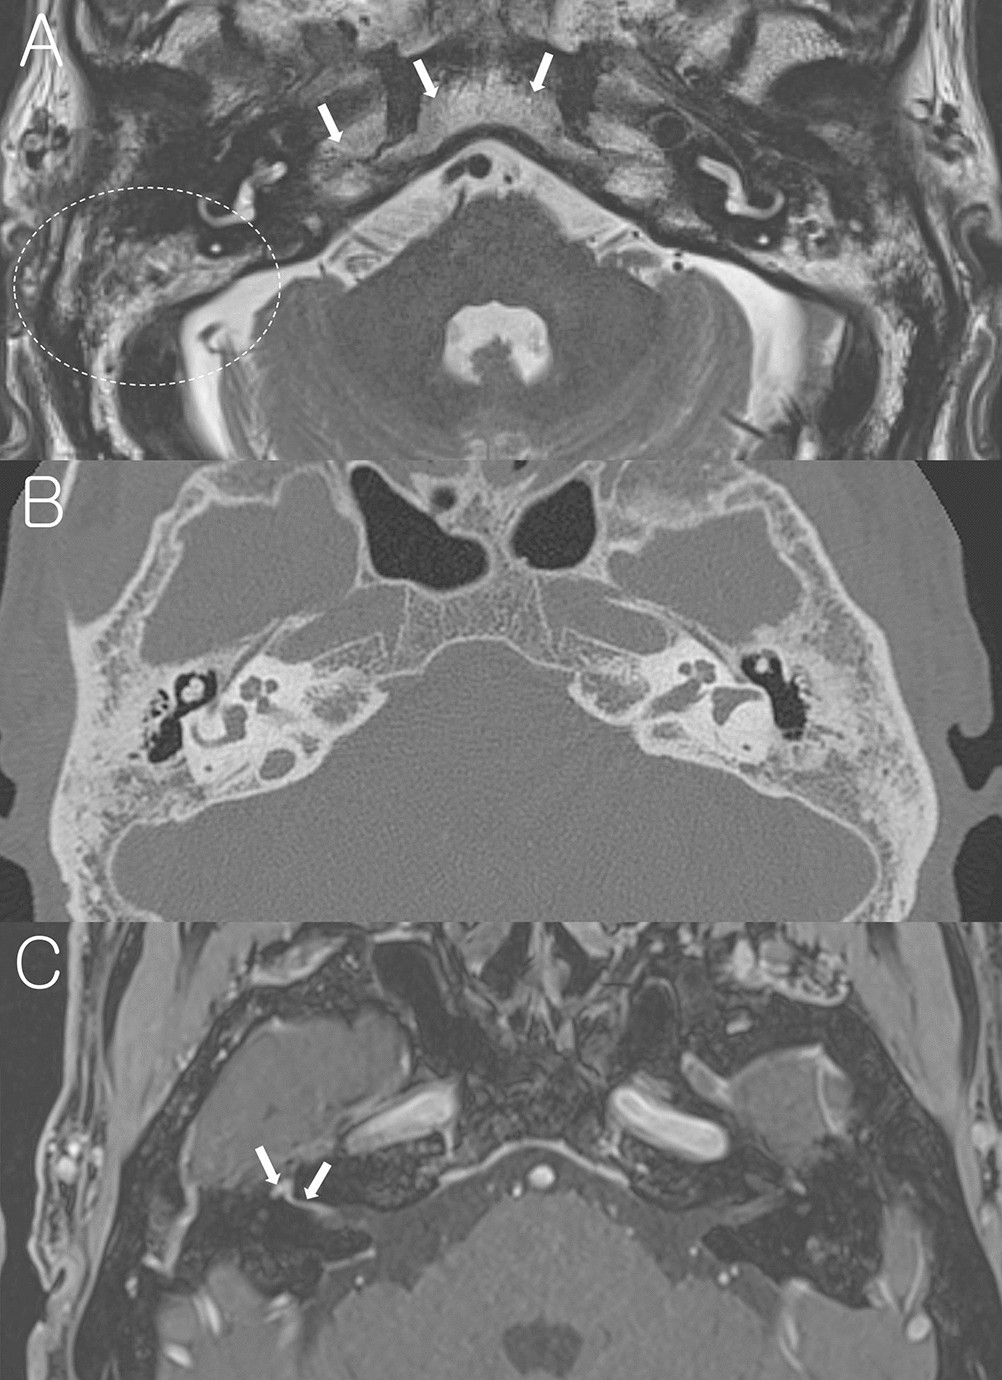

Figure 3

From: Mastoid effusion on temporal bone MRI in patients with Bell’s palsy and Ramsay Hunt syndrome

A representative case of Bell’s palsy with sclerotic mastoid. (A) Non-contrast axial T2-weighted image at the level of IAC shows heterogeneous high signal intensity in the mastoids (dotted circle) which have similar signal intensity from the adjacent clivus and petrous apex (arrows), suggesting bony sclerotic change. (B) Temporal bone CT confirms bony sclerotic change and decreased number of mastoid air cells. (C) Post-contrast axial T1-weighted image at the Bill’s bar shows enhancement of the distal canalicular, labyrinthine, genu and proximal tympanic segment of the right facial nerve (arrows).